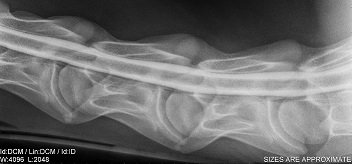

Myelograms like this one from a horse are performed using soluble nonionic organic iodides (e.g., iohexol, iopamidol, and iotolan). They are still hyperosmolar but less so than ionic organic iodides. Thus, there is a lower incidence of adverse reactions.

Image courtesy of Nora Grenager, VMD, DACVIM.